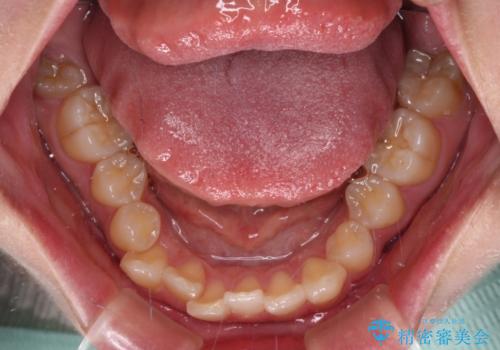

- 上下の八重歯を気にして来院された患者様です。

非抜歯矯正で歯列を整えると、治療後に口元が今よりも突出する可能性が高かったため、上下左右の小臼歯4本を抜歯し、ワイヤー装置にて矯正治療を行うこととしました。

右上の八重歯の影響で、右側は上顎歯列が前方位の咬み合わせとなってしまっていたため、上顎は第一小臼歯を、下顎は第二小臼歯を抜歯することで咬み合わせや上下正中を調整することとしました。

第二小臼歯抜歯の治療となったため、やや時間はかかりましたが、概ね予想通りの期間で治療を終えることができました。